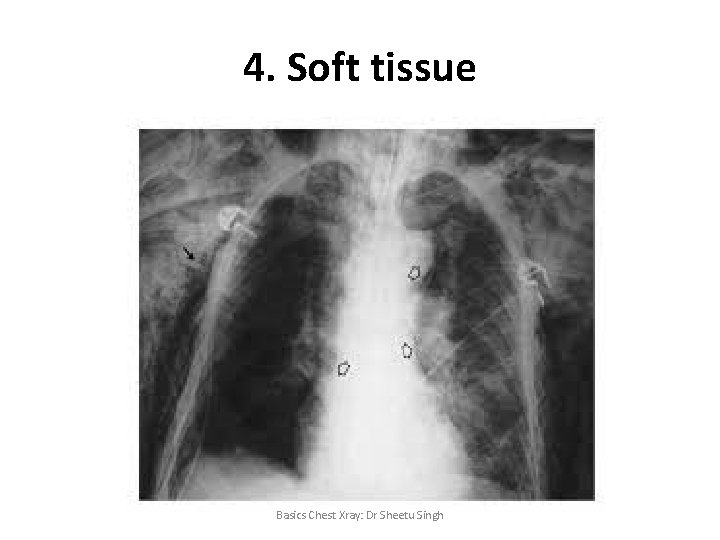

4. Soft tissue Basics Chest Xray: Dr Sheetu Singh